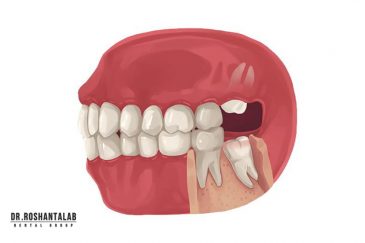

🔸 کاشت دندان یک روزه ( کشیدن و کاشت همزمان )

🔸جراحی پیشرفته نظیر سینوس لیفت